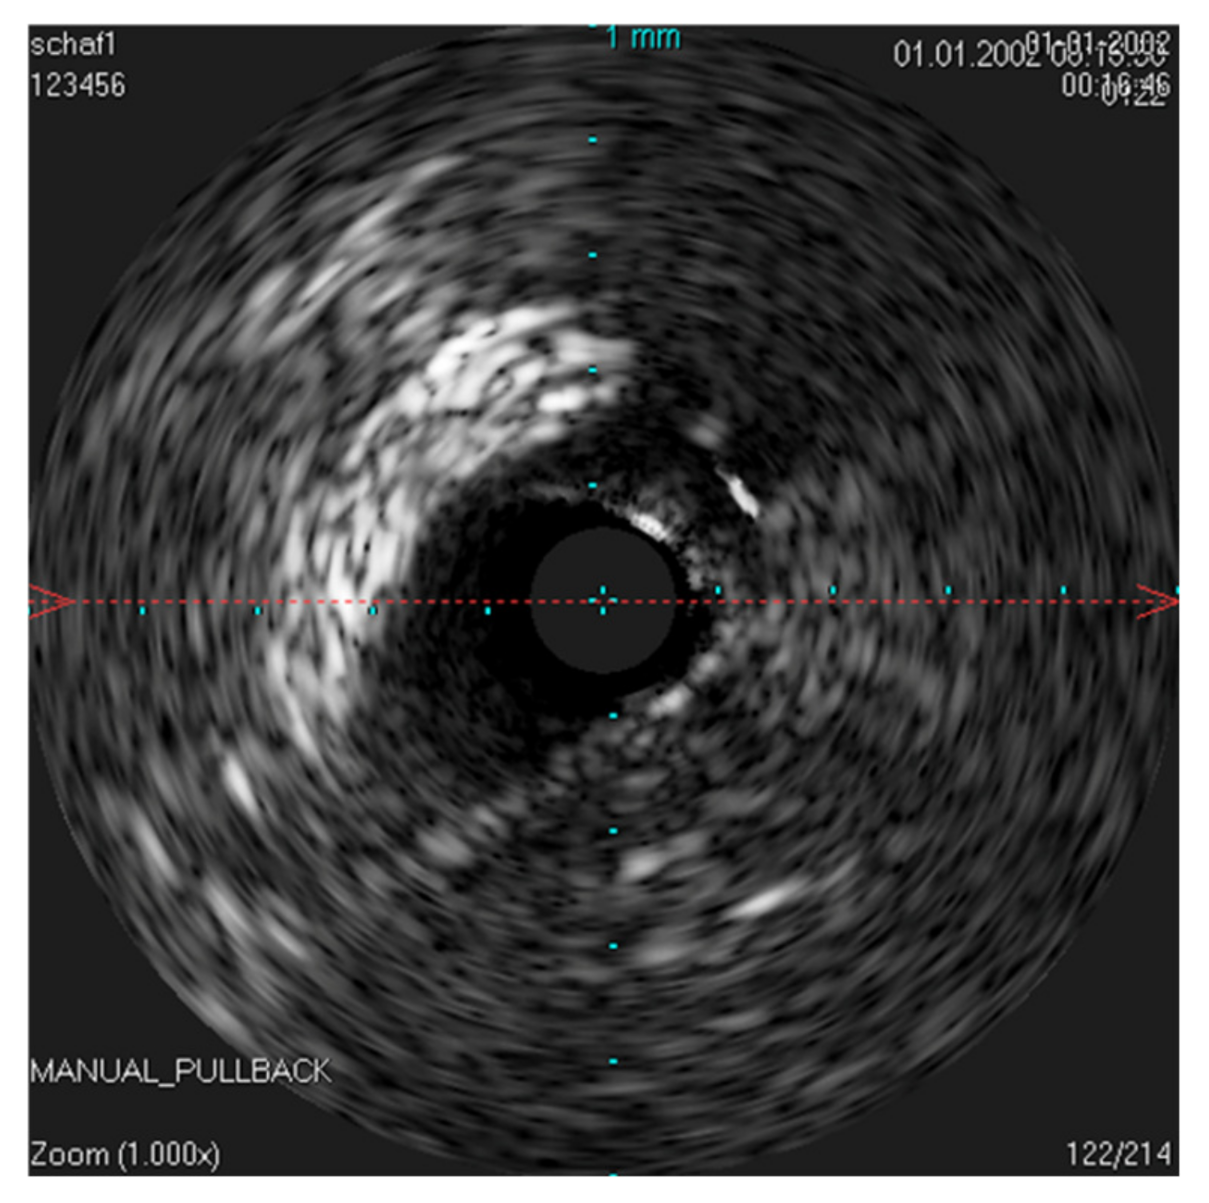

The IVUS provided a good image of the slit-formed shape of the ET (Figure 1) and the bony part with the isthmus (Figure 2) in the cross-section view. Bony structures and cartilage can be distinguished from the muscles and the Ostman fat pad. The signal transmission from the catheter to the tissue appeared to be good in all cases, even though the mucosal layer also caused some intense reflections. By flushing the ET with water (Figure 3), the lumen was more visible and became spindle shaped. Reflections at the mucosal layer were reduced.

Figure 4. Longitudinal image of the ET with the corresponding cross sections. (a) near the ET isthmus. (b) in the middle section of the ET. (c) near the pharyngeal ostium. Bone is marked with *. The bony structures represent consistent topographic landmarks. The cartilage of the ET shows low echogenicity (white arrows). Note that the dashed red line in the cross-sectional image represents the axis of the longitudinal image. The tip of the arrow points toward the lower part of the longitudinal image.